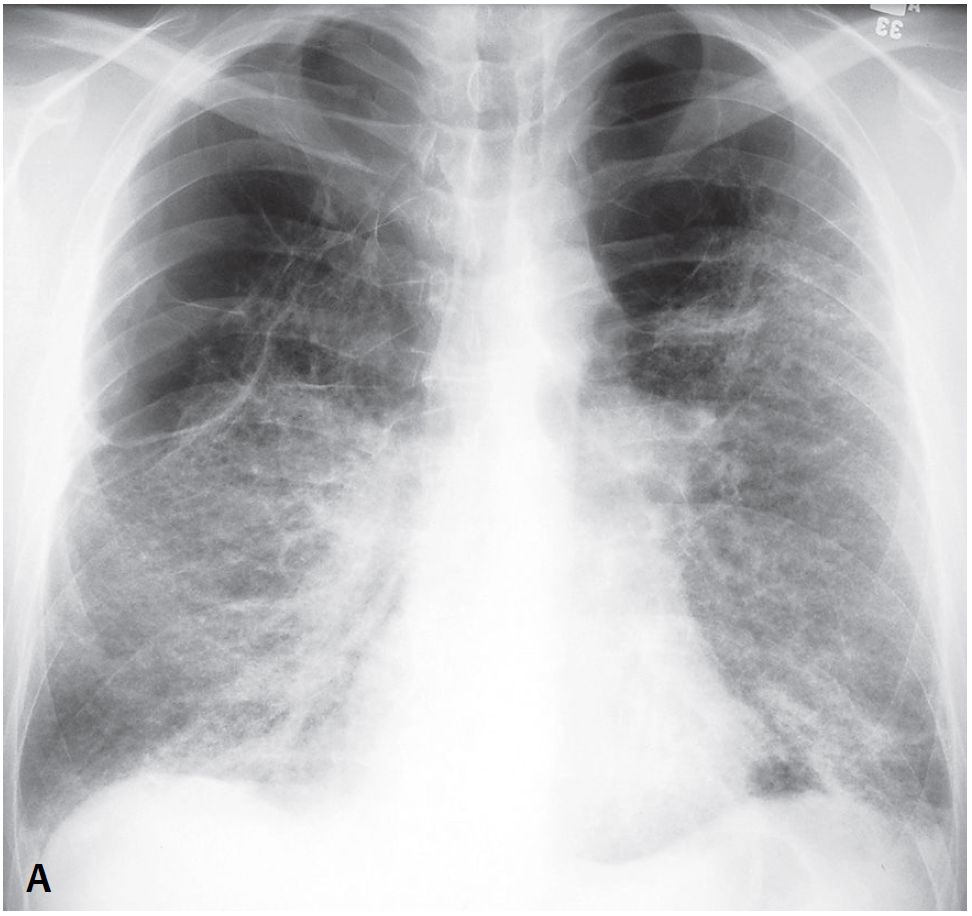

46-year-old Man with Dyspnea

A 46-year-old man presents with dyspnea on exertion.

What’s the Diagnosis ?